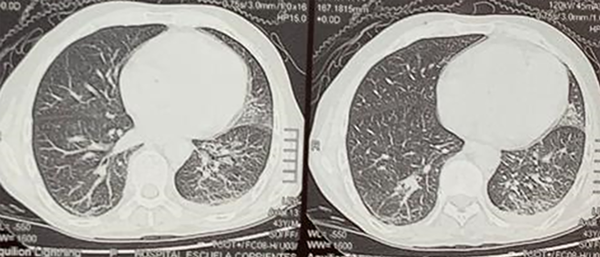

El 100% de las lesiones se ubicaron a nivel del lóbulo frontal. El 60%, a nivel precentral. El 80% presentaba lesiones múltiples y solo el 20% (1 paciente) manifestó lesión única; 3 pacientes tuvieron lesiones pulmonares asociadas (Figura 5).

Figura 5. Tomografía de tórax sin contraste que evidencia compromiso pulmonar asociado en paciente con diagnóstico de absceso cerebral por Nocardia spp.